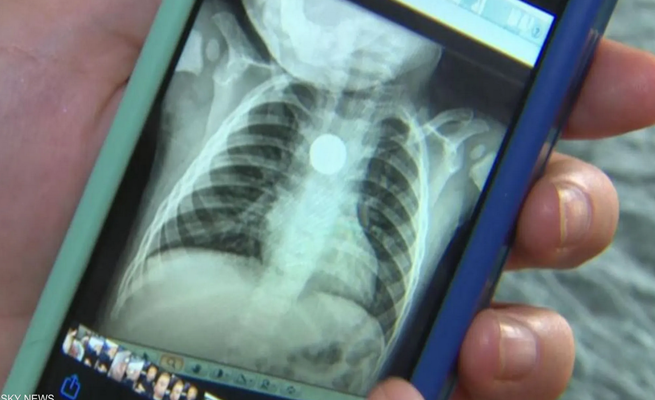

وبعدما أخذته إلى المستشفى، أظهرت صورة الأشعة السينية أن هناك بطارية زر في المريء، وقال الأطباء إنه في حال لم تجر العملية بسرعة فسوف يموت الطفل.